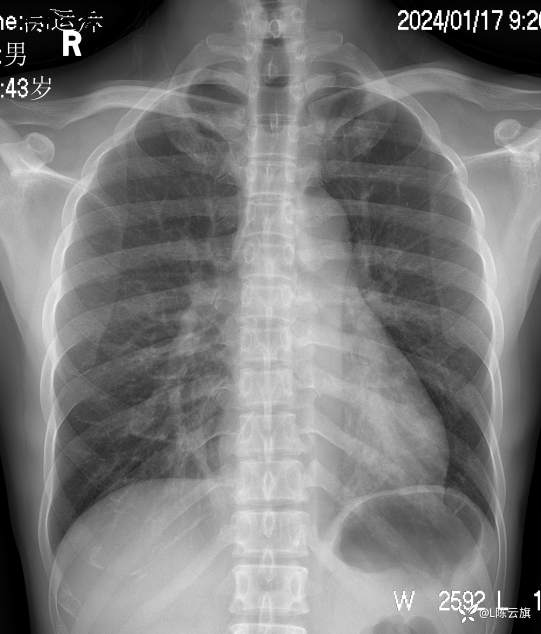

胸片2: